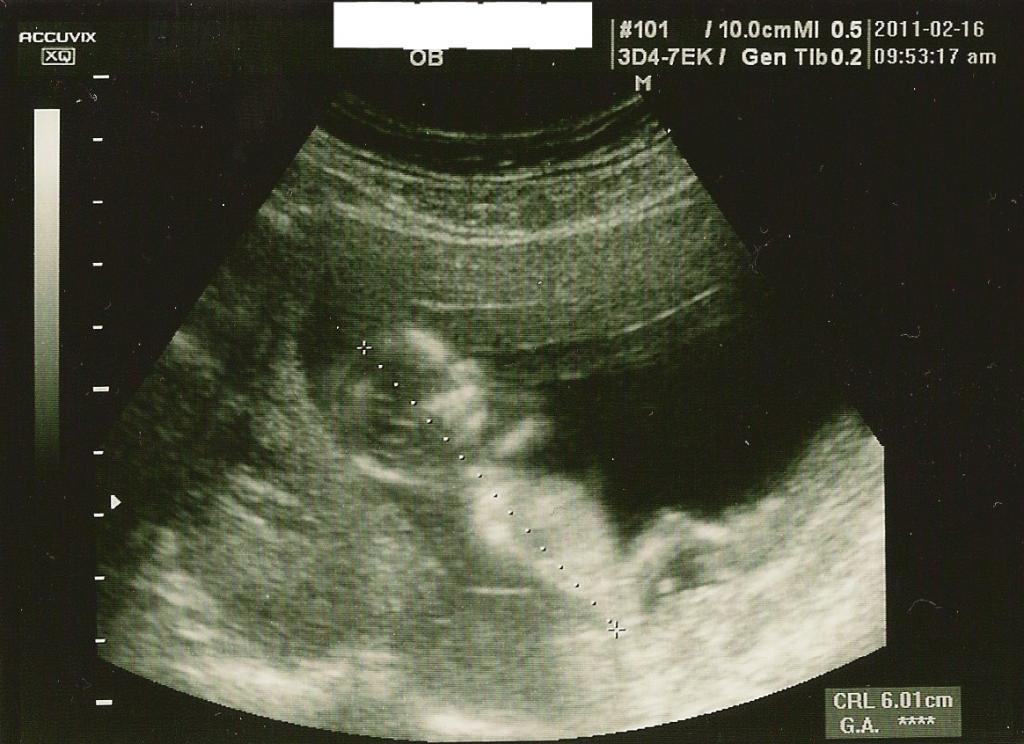

12週 赤ちゃん 大きさ 平均- 11週〜12週の赤ちゃんってこんな感じ。 だいぶ人間の形になってきました。 9週から12週手前まで検診が3週間空いたので、23cmから5cmに急成長してました。 頭からお尻が5cmで、足は4cmあるそうです。 妊娠12週で受検できる出生前診断 妊娠12週は、 妊娠初期から妊娠中期へと近づいていく時期 です。超音波検査のエコー写真では、胎児の見た目により人間らしさが出てきます。エコー検査のほかにも、出生前診断には多くの検査方法があります。

妊娠12週目エコーで性別やダウン症が判明?つわりが軽くなる時期 胎児の大きさの平均 妊娠12週目(妊娠4ヶ月目の1週)の赤ちゃんの大きさの平均は 60~70ミリで、体重は15~グラム程度 ですが、赤ちゃんらしい姿に進化している時期です。 赤ちゃんは呼吸の練習も始め赤ちゃんの状態 身長 ~40mm 体重 ~約g 8週頃はほぼ半分が頭部、8週後半から少しずつ手足がわかるようになる。胴体や手足が発達して3頭身になり、11~12週頃になると、目や鼻の形も見えやすくなる。 ママのからだ 子宮の大きさ 握りこぶしぐらい